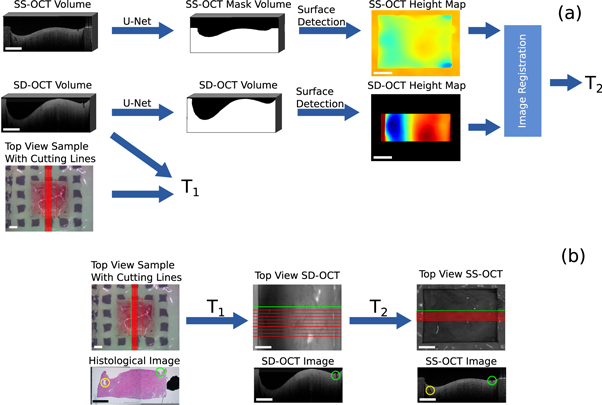

Standard image High-resolution image2.3.1. Finding OCT images corresponding to the histological cuts

This section describes the first step of the processing pipeline. It demonstrates how the cutting lines Cwl

= x, y were transferred from the white light image of the sample onto the OCT volumes, thereby determining the corresponding OCT images for each histological cut. Figure 4 shows the processing steps. The position of the cutting lines on the OCT volume of SD-OCT were known, since the white light image was acquired by this system. This means that the position of the OCT field of view and the spatial relations between the cutting lines and the field of view of the white light image were used to create a transformation matrix  , which considers translation, rotation and scaling. T1 was applied to the cutting lines Cwl

in order to transfer them onto the SD-OCT volume. This gained the position of the cutting lines on the SD-OCT volume Csd

.

, which considers translation, rotation and scaling. T1 was applied to the cutting lines Cwl

in order to transfer them onto the SD-OCT volume. This gained the position of the cutting lines on the SD-OCT volume Csd

Figure 4. Overview of the work-flow to find OCT images corresponding to the histological images: (a) processing pipeline to determine the transformation matrices in order to transfer the cutting lines onto the OCT volumes. (b) Extraction of corresponding OCT images along the transferred cutting lines. The green and yellow markers show corresponding structural features. The rectangle in the bottom left of each image has the length of 1 mm.

Standard image High-resolution imageIn order to transfer the cutting lines Csd

onto the SS-OCT volume, an affine transformation  was calculated between the SD-OCT volume and the SS-OCT volume. T2 allows the transformation of Csd

onto the SS-OCT volume, resulting in the cutting lines Css

. The affine transformation matrix T2 considered rotation, translation and scaling between the two volumes. T2 was iteratively determined reducing the dissimilarity between topological height maps, which were generated from the OCT volumes (Maes et al

1996). The dissimilarity was computed through the mutual information and the optimization was done with the help of Powell's optimization method (Powell 1964). The topological height maps were used for the registration, because the height information is independent from the acquisition wavelength and intensity. The topological information was calculated from binary masks, which differentiate between tissue and agarose (foreground) and air (background). The mutual information was used because only relative height differences could be retrieved from the OCT images. This is because OCT can only measure distances with respect to the position of the reference arm of the OCT system. This means that there is a constant height shift between the height maps of one sample. The height value was defined as the depth value of the edge pixel between foreground and background.

was calculated between the SD-OCT volume and the SS-OCT volume. T2 allows the transformation of Csd

onto the SS-OCT volume, resulting in the cutting lines Css

. The affine transformation matrix T2 considered rotation, translation and scaling between the two volumes. T2 was iteratively determined reducing the dissimilarity between topological height maps, which were generated from the OCT volumes (Maes et al

1996). The dissimilarity was computed through the mutual information and the optimization was done with the help of Powell's optimization method (Powell 1964). The topological height maps were used for the registration, because the height information is independent from the acquisition wavelength and intensity. The topological information was calculated from binary masks, which differentiate between tissue and agarose (foreground) and air (background). The mutual information was used because only relative height differences could be retrieved from the OCT images. This is because OCT can only measure distances with respect to the position of the reference arm of the OCT system. This means that there is a constant height shift between the height maps of one sample. The height value was defined as the depth value of the edge pixel between foreground and background.

Standard image High-resolution imageThe resulting affine transformation T2 was then applied to the cutting lines Csd of the SD-OCT to complete the transformation onto the SS-OCT. An example for a successful registration is shown in figure 4. The histological section and the corresponding OCT B-scans were extracted along the same 'cutting line'. The green and yellow marker show visible structural features, which can be seen in all three images. The overall surface contour also shows similarities between the images.